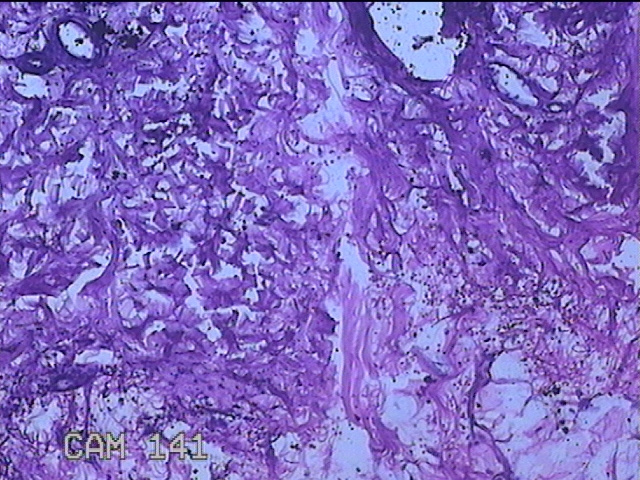

左侧臀部结节

性别

男

年龄

40岁

临床诊断

皮下结节

一般病史

发现左侧臀部结节1年余。

标本名称

大体所见

灰白粉红色组织1.3x0.8x0.3cm一块,表面带梭形皮肤1.3x0.8cm,皮下见结节1.3x1x0.7cm一个,切开结节呈实性,切面灰白粉红色,质软。

图4